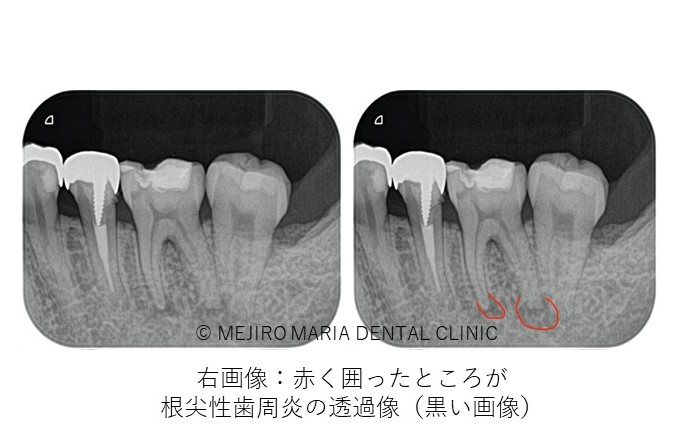

治療終了後、良好に根の中にバイオセラミックが充填され封鎖できていることを確認し(画像A)、3ヶ月後の経過観察にて、痛みや違和感がないことはもちろんのこと、術前、術後に確認できていた根尖性歯周炎の透過像の縮小を確認(画像B)し経過が良好であると判断しました。

経過観察当日に被せ物(最終補綴処置)の型取りを行い、次回セットし終了しました。次回は1年後に経過観察を行う予定です。

また、個人差はありますが、治療後の病変(根尖性歯周炎)のレントゲン像に変化が見られるのはおおよそ3ヶ月後であることから、当院では根管治療終了3ヶ月後に経過観察を行い外科的歯内療法(歯根端切除術)の必要性を判断しております。